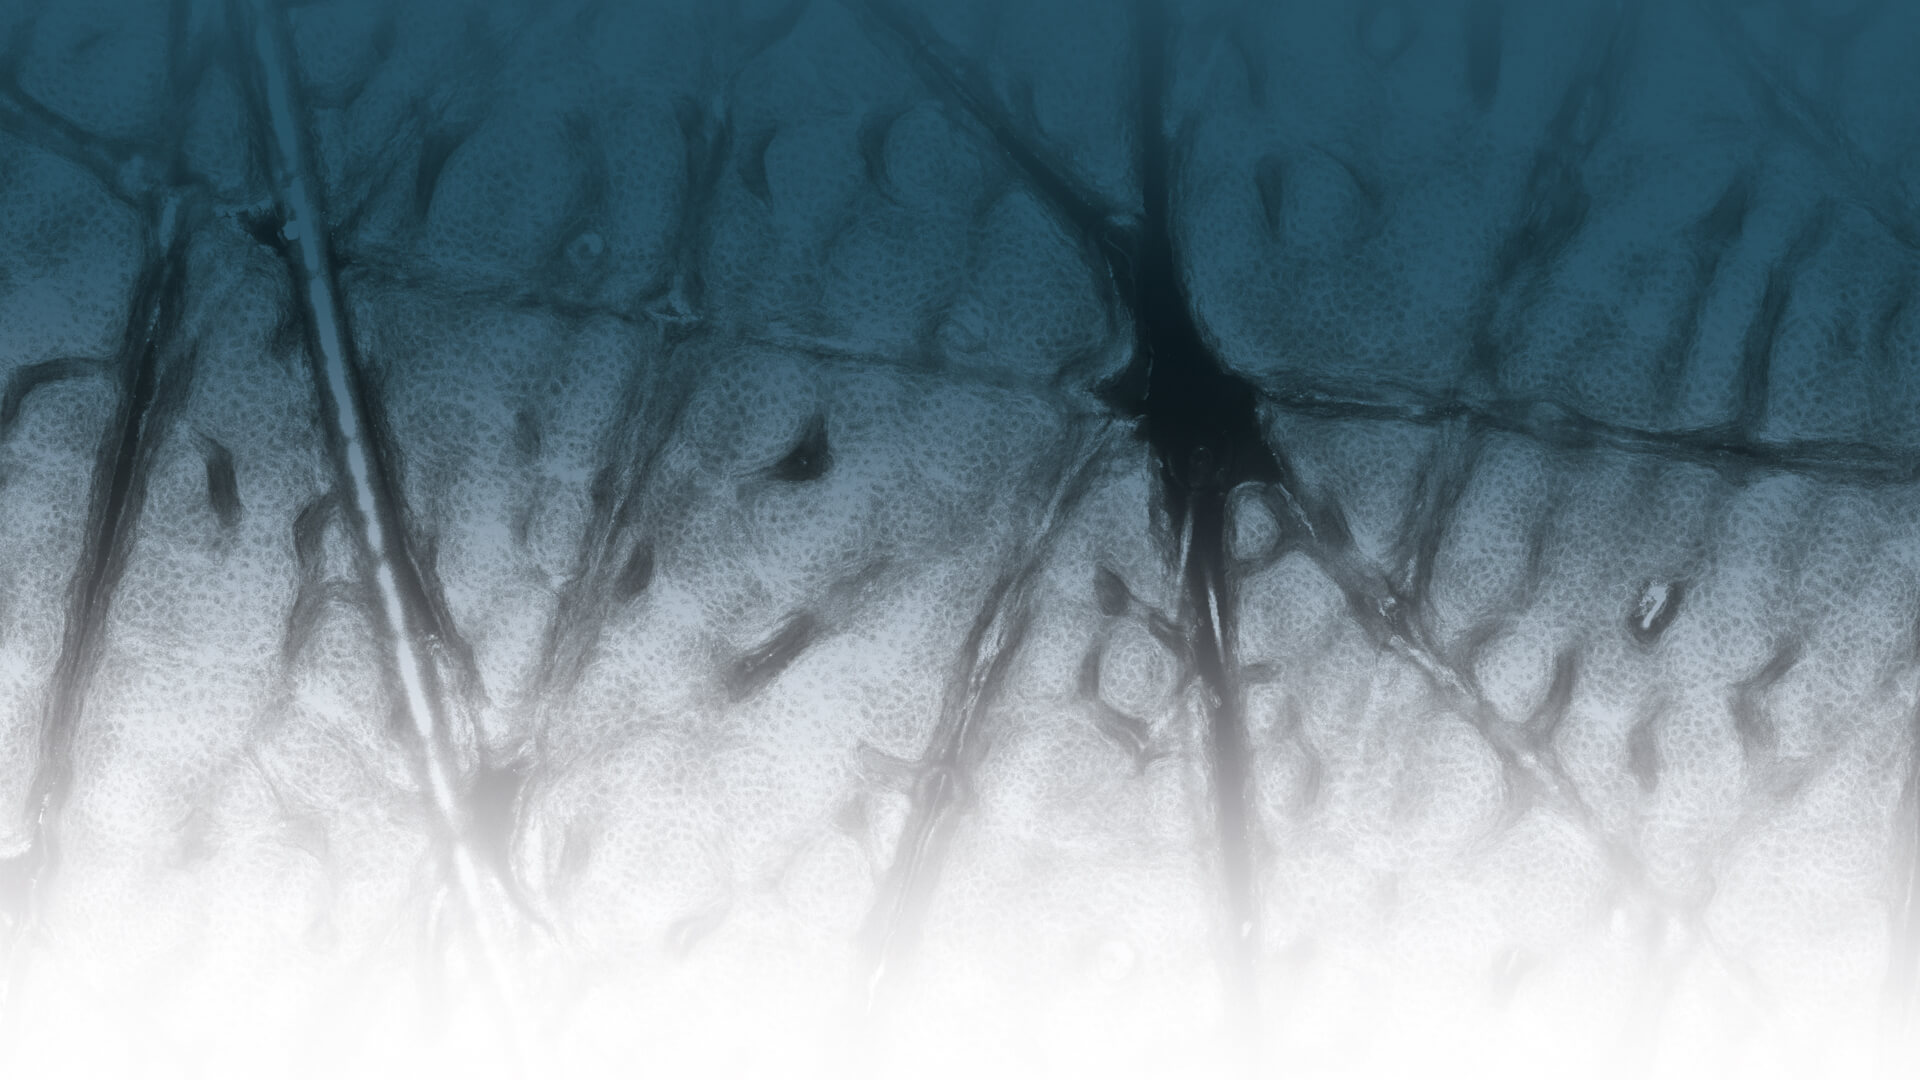

Layer by layer. See beneath the skin. For best patient care.

In Vivo examinations with the VivaScope technology using confocal laser scanning microscopy (CLSM) allow for an optical biopsy using a non-invasive procedure. See the different skin layers of your patients in real time.

All images courtesy of Prof. Dr Elke Sattler, Dr Martina Ulrich, Prof. Dr Julia Welzel